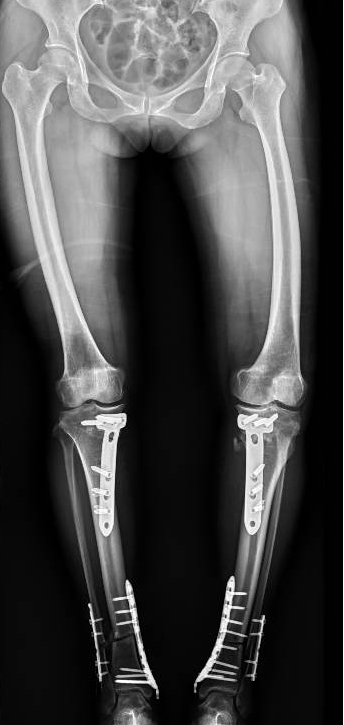

手術(shù)前 手術(shù)后

2024年8月13日,手術(shù)順利進(jìn)行。

手術(shù)很成功!經(jīng)過精心的治療和護(hù)理,董阿姨在9月順利出院。當(dāng)她再次站在鏡前時(shí),她驚喜地發(fā)現(xiàn)自己仿佛長(zhǎng)高了一截,那份曾經(jīng)讓她備受折磨的疼痛與不適也逐漸消失了。